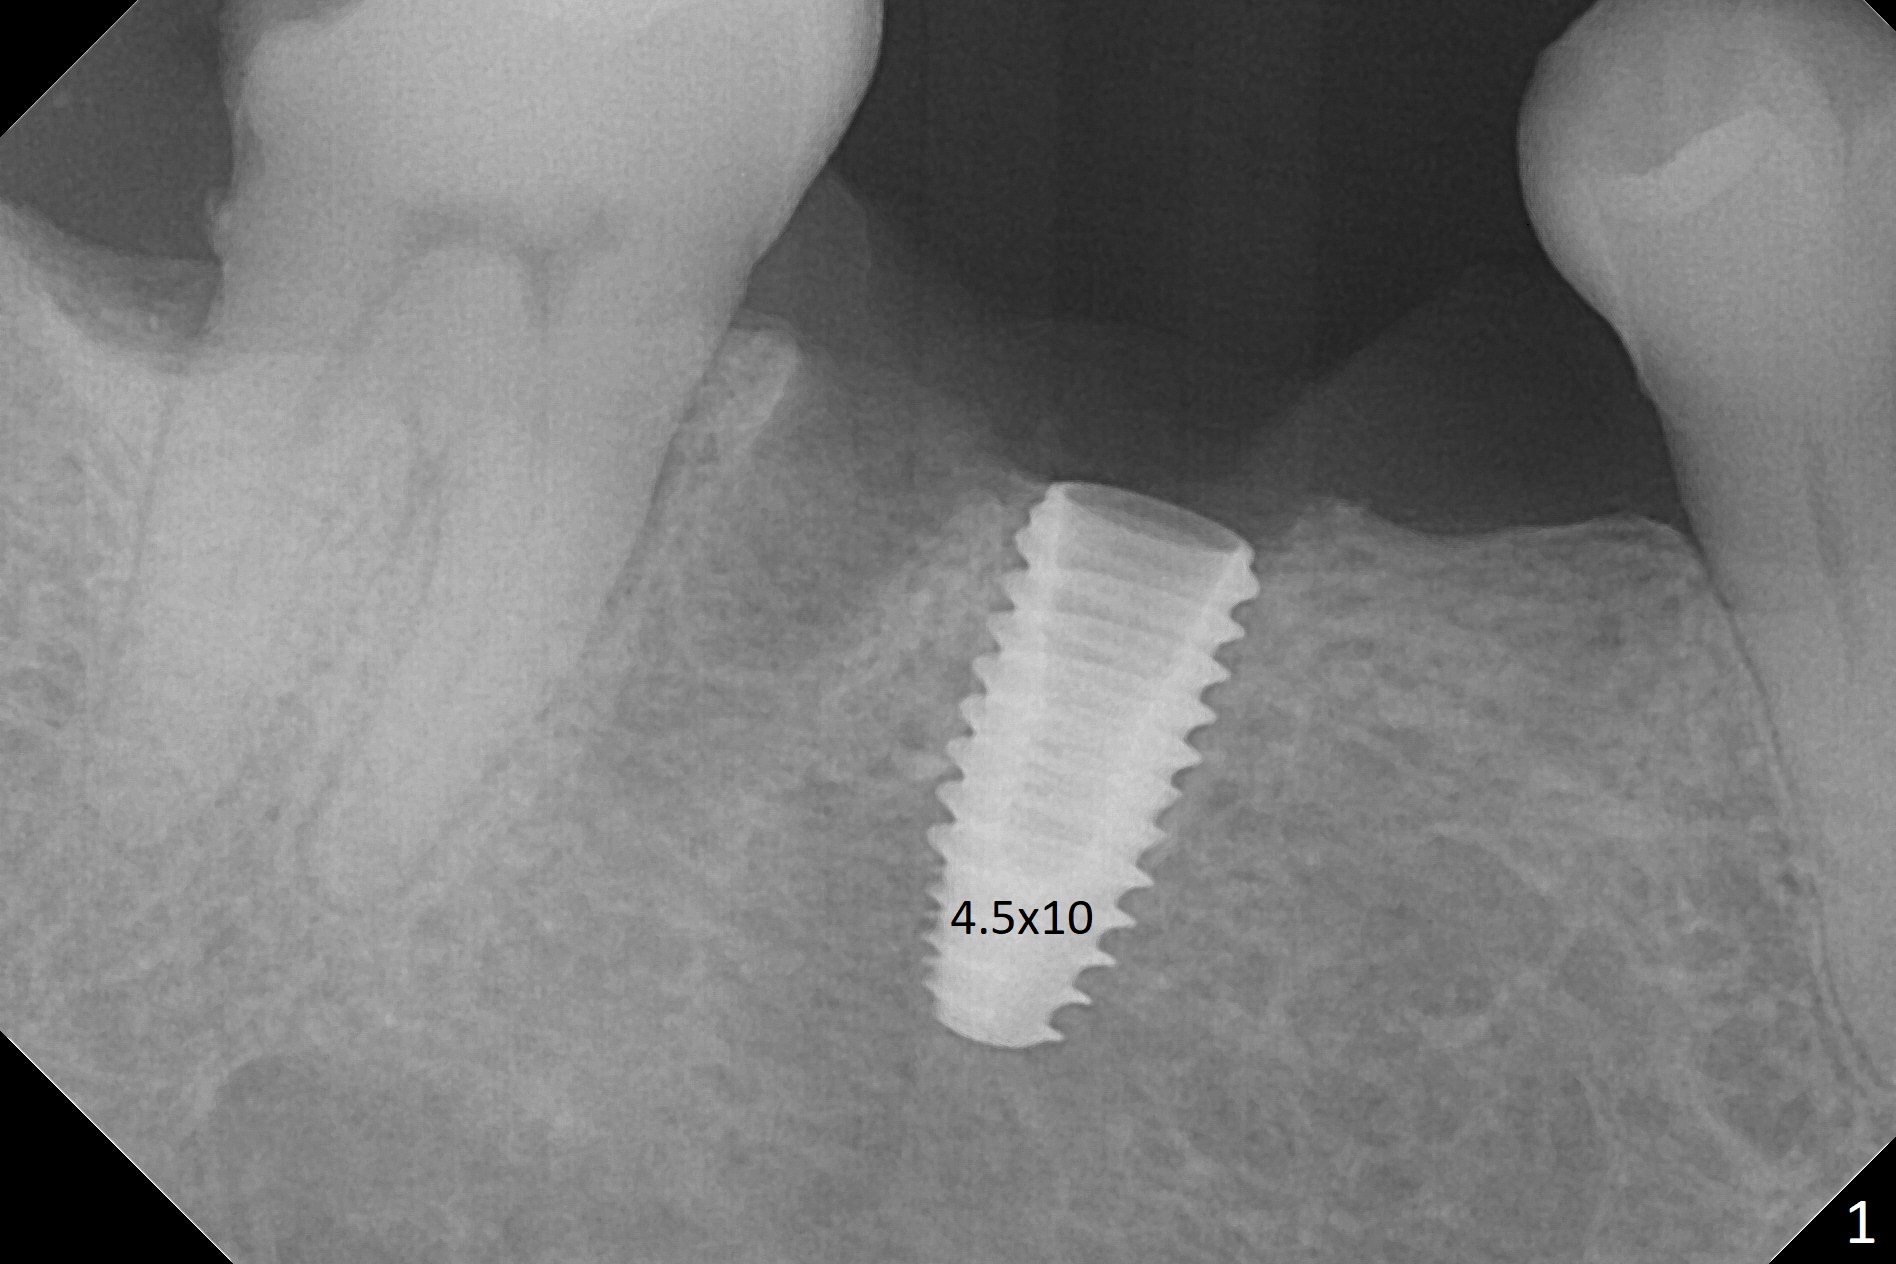

Because of severe pain, block anesthesia is administered prior to extraction. The mesial socket of the tooth #30 is deep with granulation tissue. A 4.5x10 mm dummy implant is placed with < 40 Ncm following sequential osteotomy until 4x13 mm over the septum (Fig.1 (low density)). After 4.5x13 mm drill, a 5x10 mm dummy implant is inserted with <40 Ncm (Fig.2). Since the Inferior Alveolar Canal is invisible (Fig.1,2 (pan should have been taken)), a 5x11.5 mm implant is placed with <20 Ncm. When a 6.5x5.5(3) mm abutment is placed, the underlying implant is turned (Fig.3). With collagen plug is placed in the distal socket and Vera graft around the implant, an immediate provisional is fabricated and relined. When it is seated, it has mobility. In fact the provisional should be locked into the edentulous area while it is malleable. To prevent low primary stability, osteotomy should be under prep, since the implant (red circle) contacts only two bony surfaces, i.e., the mesial (M) and distal (D) walls of the mesial socket (Fig.4 (occlusal view) black oval). There are gaps buccally (B) and lingually (L). In case of low stability, a healing screw or abutment should be placed; the remaining socket is closed with suture. The provisional is loose 19 days postop; it is removed by sectioning. A healing screw is placed. Twelve days later, the wound heals (Fig.5). The patient returns for uncover 8 months postop; although the implant has osteointegrated apparently, the crestal bone resorbs to the implant plateau level (Fig.6 arrow). It seems that the immediate implant should be routinely placed 2-3 mm deeper. The open margin is closed with composite when the abutment/crown is removed after cementation (Fig.7).